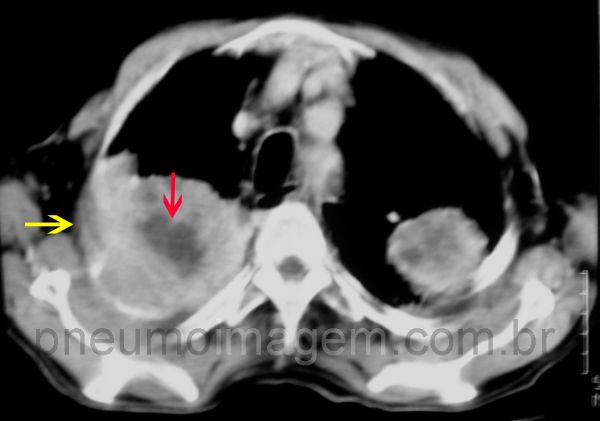

O adenocarcinoma faz parte do grupo dos carcinomas não pequenas células (CPNPC) e é um dos quatro principais tipos de neoplasias do pulmão. Geralmente ele se apresenta como um tumor periférico. Nesse caso, massas periféricas bilaterais nos lobos superiores.

Observe que a lesão no lobo superior direito invade a parede torácica e leva à corrosão do arco costal (seta).

Corte tomográfico demonstrando as massas apicais. Observe a necrose central (seta vermelha) e a invasão da parede torácica (seta amarela).

CT scan showing the apical masses. Observe the central necrosis (red arrow) and the invasion of the chest wall (yellow arrow).